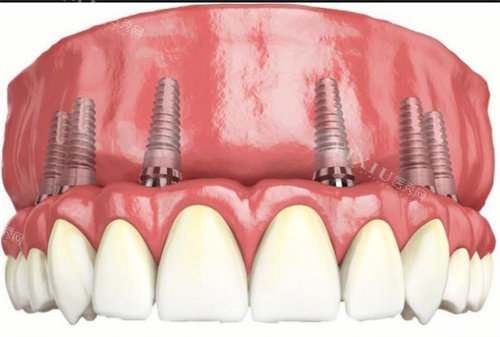

牙槽骨条件差(比如骨量不足、骨质疏松):德国植体表面粗糙,能加速骨结合,降低“种不活”风险。 缺牙位置在磨牙区(承担咬合力大):德国植体强度更高(抗压值超500MPa),长期用更稳。 对“一劳永逸”有执念:德国品牌临床数据显示,10年留存率超95%(韩国约90%)。

适合韩国种植体的情况:

预算有限(5000-8000元):韩国品牌集采后价格友好,适合学生党、刚工作的年轻人。 牙槽骨条件较好(骨量充足、无炎症):韩国植体足够满足日常使用,没必要多花钱。 短期用牙需求(比如过渡性修复):比如准备矫正牙齿,先种颗韩国植体“占位置”,后期换德国的也方便。